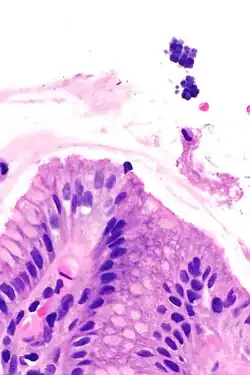

| Gastric mucosa and Sarcina on upper right. H&E stain. | |

Sarcina is a genus of gram-positive cocci bacteria in the family Clostridiaceae.[2][3][4] A synthesizer of microbial cellulose,[5] various members of the genus are human flora and may be found in the skin [6] and large intestine.[7] The genus takes its name from the Latin word "sarcina," meaning pack or bundle, after the cuboidal (2x2x2) cellular associations they form during division along three planes.[8]